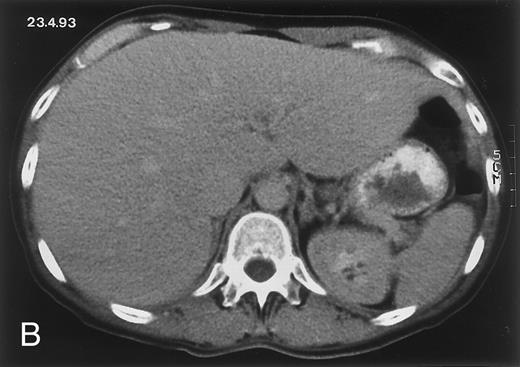

Radiologic evolution in patient A. (A) Postcontrast abdominal CT scan on March 16, 1993 shows multiple small hypodense areas in all segments of the liver, suggestive of hepatic candidiasis. Seven days previously, the patient had recovered from severe neutropenia after the first cycle of chemotherapy for AML. (B) On April 23, 6 days after the neutrophil count had dropped below 500/μL in the second cycle of chemotherapy, there is no evidence of focal lesions on postcontrast CT scan. (C) On June 18, when neutrophils were normalized for 46 days, CT scan again shows multiple small abscesses.

(D) On August 23, 15 days after the neutrophil count had dropped below 500/μL in the third chemotherapy cycle, focal liver lesions clearly decreased in size and number. (E) On September 30, 35 days after neutrophil recovery, multiple hepatic abscesses are seen (arrowhead). To show maximal extent of lesions the scan shown is at a slightly different level. (F) On June 16, 1994, 230 days after neutrophil recovery, the CT scan has normalized.